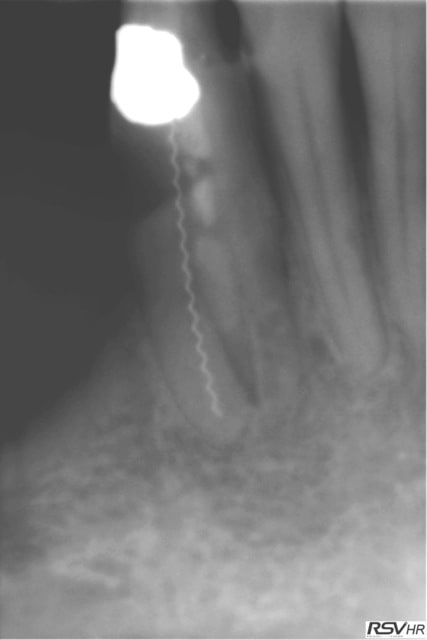

28/03/2007 à 15h14

moi aussi je les adore, mais des fois j'hesite, là je crois que je vais renvoyer parceque je n'arrive meme pas a savoir ce qui a été fait, un, deux, trois canaux a l'origine, ou une grosse fausse route au milieu (non quand meme), et puis meme, ensuite, elle va encore durer cette canine?